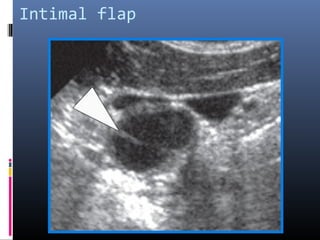

Intimal flap

Dissecting aneurysm